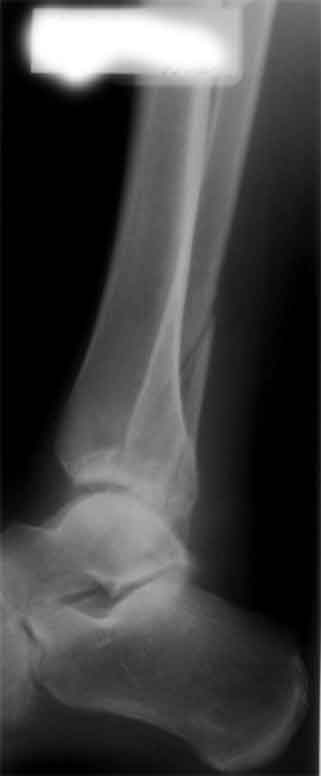

Здесь представлено решение похожей проблемы. Больной в течение года лечился консервативными мерами, и боли в голеностопе были основным показанием к операции.

Проведена обычная стандартная процедура по исправлению неудовлетворительного состояния голеностопного сустава, где кроме удлинения малоберцовой с применением compression tension device за проксимальный конец пластины, проведено замещение трикортикальным графтом из крыла, освобождение синдесмоза и медиальной щели от

фибротических масс с фиксацией.